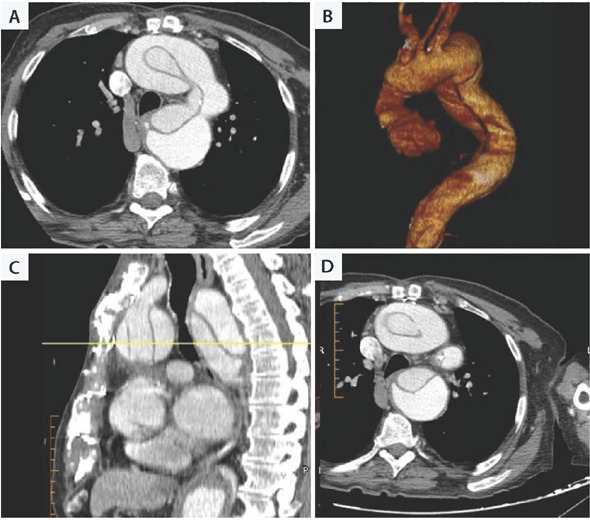

Reentry to the mediastinum when the ascending aorta aneurysm is adherent to the sternum is characterized by high risk of aneurysm rupture during sternum opening. In such cases, often cardiopulmonary bypass via peripheral vessels is instituted, and reentry done in deep hypothermia and circulatory arrest. To reduce both risks of aneurysm rupture during resternotomy and those related to prolonged cardiopulmonary bypass time, we present a surgical approach consisting of a two-stage sternotomy to avoid the risky zone and extra-anatomic epiaortic vessels anastomoses.